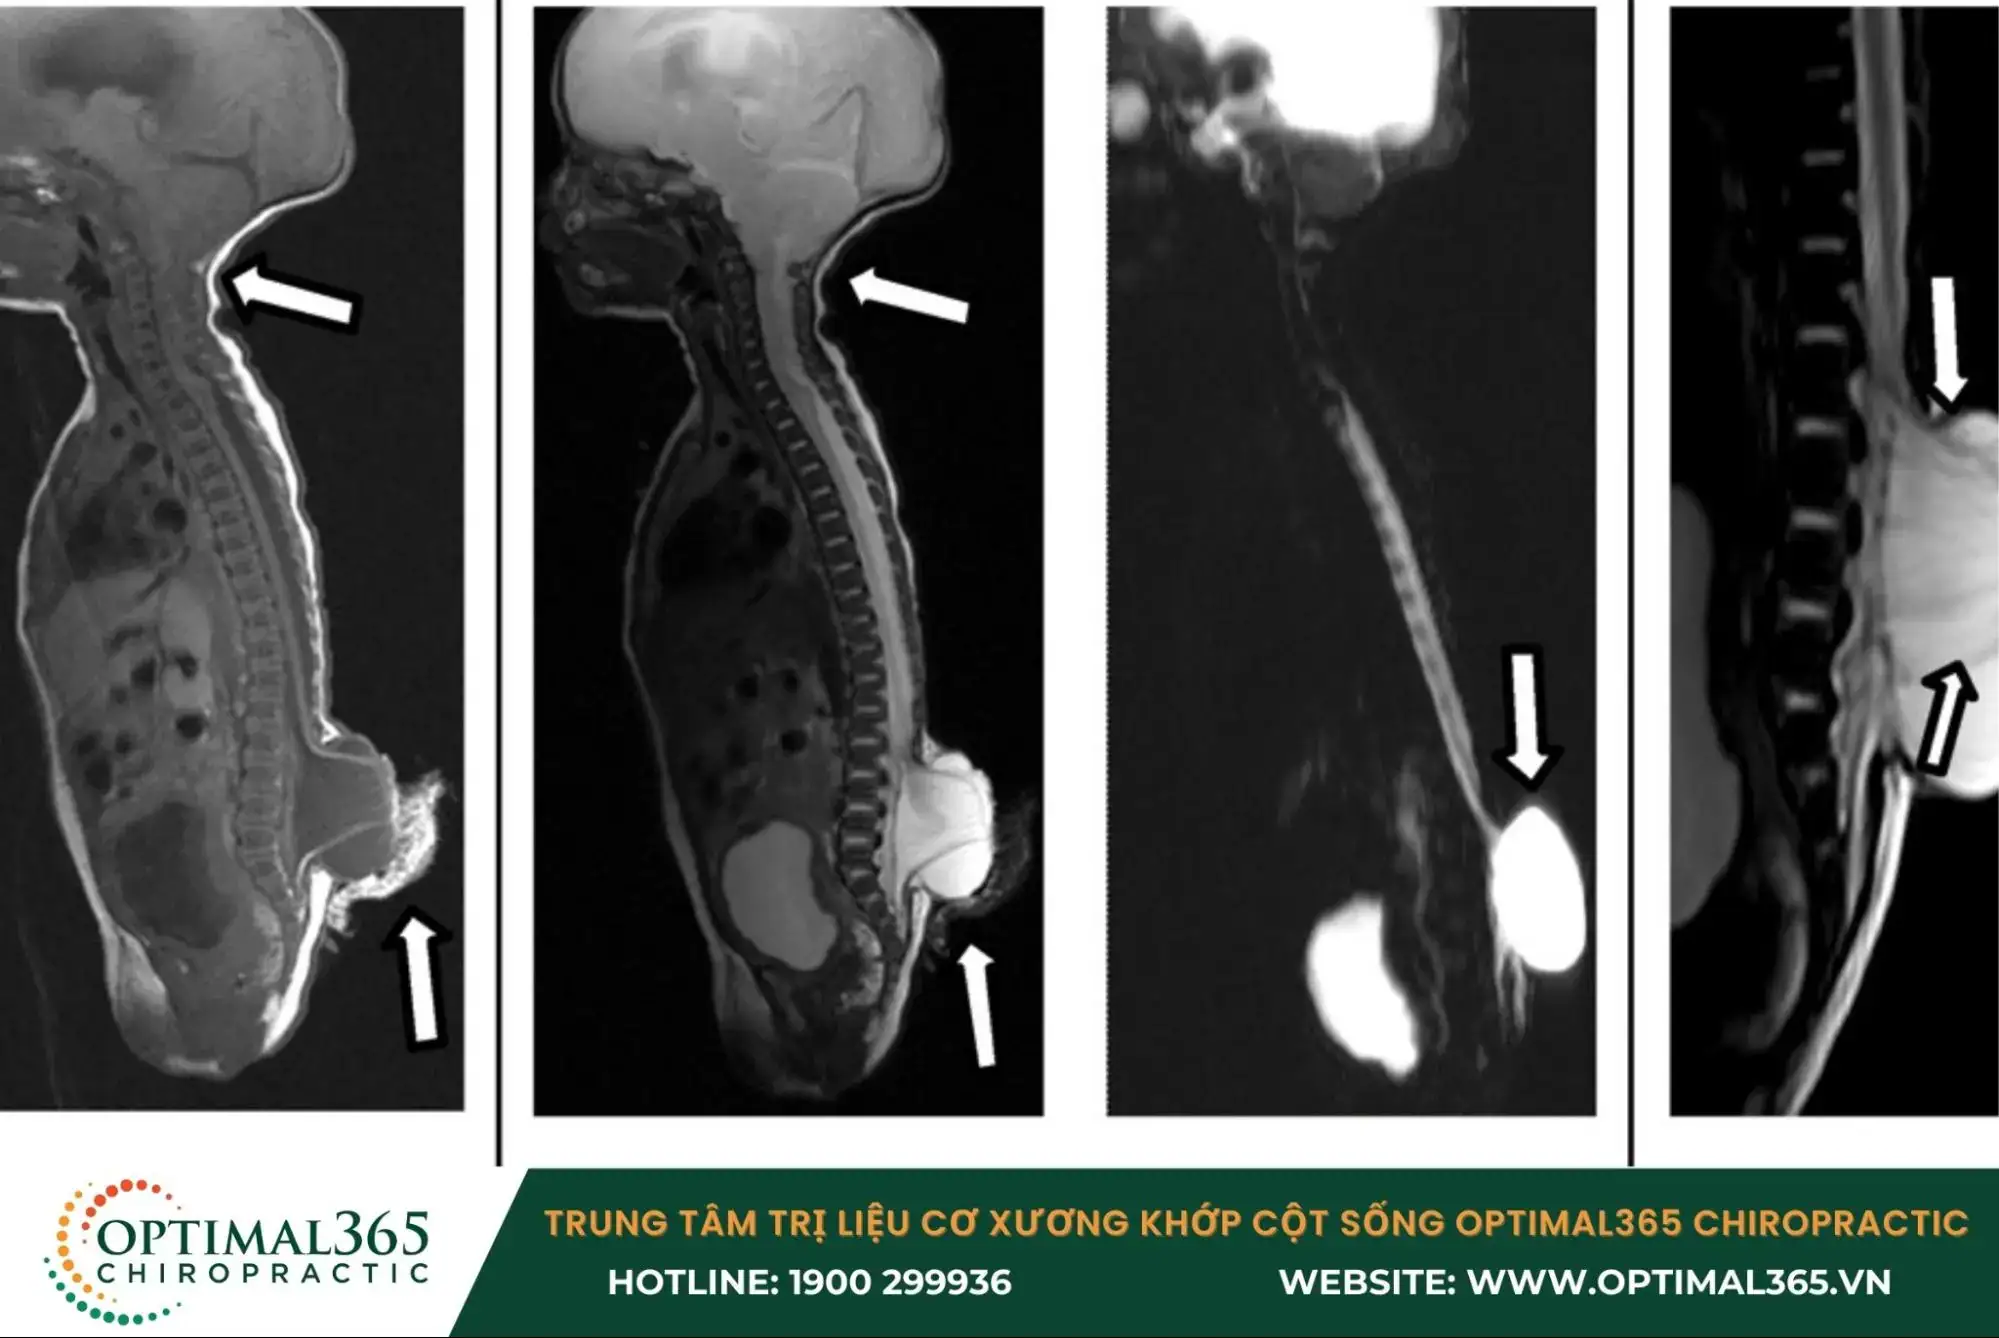

- Chụp X-quang: Đây là phương pháp cơ bản được sử dụng để phát hiện tổn thương gai đôi cột sống. Lưu ý rằng chụp X-quang nhanh chóng, dễ thực hiện và tiết kiệm chi phí, nhưng trẻ phải tiếp xúc với tia X.

- Chụp cắt lớp vi tính (CT scan): Kỹ thuật này cung cấp hình ảnh chi tiết của cột sống và có thể phát hiện các vấn đề như não úng thủy hoặc thoát vị dịch não tủy. Nhưng cũng cần lưu ý phương pháp CT cho hình ảnh rõ nét, nhưng cũng phải tiếp xúc với tia X.

- Cộng hưởng từ (MRI): Phương pháp này giúp đánh giá chi tiết các tổn thương của tủy sống và các vấn đề liên quan đến phần mềm xung quanh. MRI không sử dụng tia X, vì vậy không có nguy cơ phơi nhiễm bức xạ và rất hiệu quả trong việc phát hiện các bất thường, tổn thương.